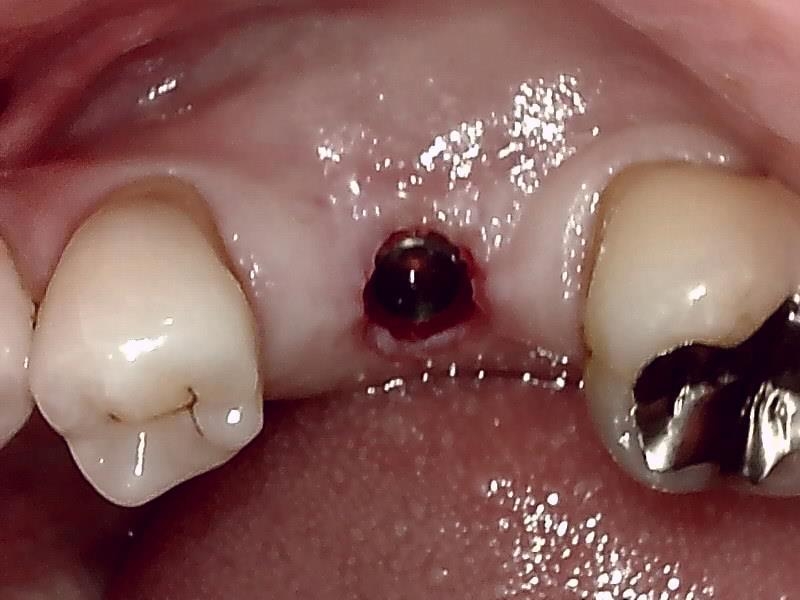

術中インプラント埋入した状態は良好です。

術前の時は瘦せていた顎堤が適切なグラフト手技により

しっかりした厚みのある顎堤が隆起している。

インプラント埋入後、10ヶ月経過した健全な顎堤の状態です。